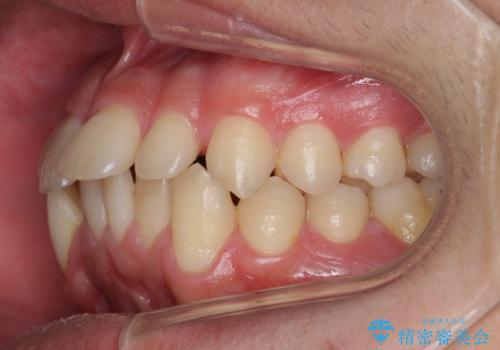

右下に乳歯が残っていましたが、後に続く永久歯がありませんでした。

乳歯も根が吸収しており長くは持たない状況でしたので、まず乳歯を抜歯し、他の歯を矯正治療で歯を並べてからインプラントで補綴しました。

先にインプラントをしてしまうと、矯正治療で周りの歯を動かす事ができなくなってしまいます。

矯正治療→インプラントの順で行います。